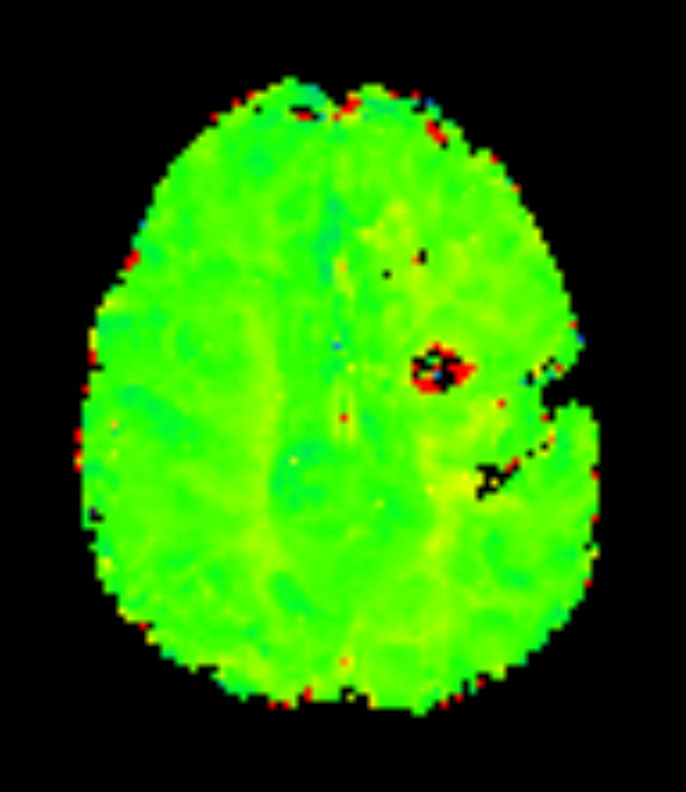

Axial T2* Perfusion - rCBF

-